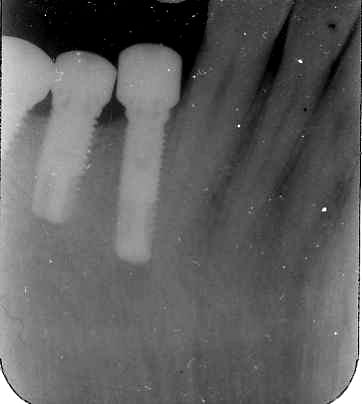

Depuis la pose de l'implant en 44 il y a 4 jours, la 43 est sensible à la pression et occasionne de violentes douleurs. Que faut-il faire ? Attendre et traiter ultérieurement la 43 si ça ne rentre pas dans l'ordre, ou retirer l'implant tout de suite. Dans l'immédiat, l'inflammation est calmée par une prescription de solupred sur 4 jours.

Ta radio ne permet pas d'objectiver si il y a un souci réel de proximité de col 44 collet 43.

A toi de nous dire si tu es à moins de 2 mm du collet de 43.

Idem pour l'apex, faut faire une autre incidence pour voir si tu es réellement dans le ligt de 43, dans la racine ou simplement dans un plan différent.

L'image radioclaire de forme ovalaire au bout de l'implant ne serait pass le foramen mentonnier??

si oui je pense que c'est plutot du a cette compression..

La situation serait très atypique, et on ne voit ni le canal dentaire ni le canal incisif.

C'est plutôt à mon humble avis un "excès" de forage qui a peut-être lésé le paquet vasculonerveux de 43.

Je viens de voir ta radio. A mon avis, tu es bel et bien dans la dent et pas seulement dans le ligament. Penses-tu pouvoir dévisser facilement ton implant ? Quelle a été ta sensation lors de la pose ?